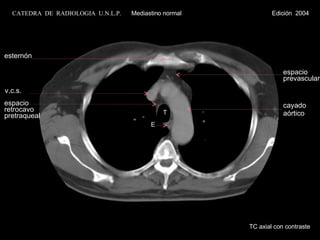

T E v.c.s.cayado aórtico espacio prevascular esternón espacio retrocavo pretraqueal TC axial con contraste CATEDRA DE RADIOLOGIA U.N.L.P. Mediastino normal Edición 2004